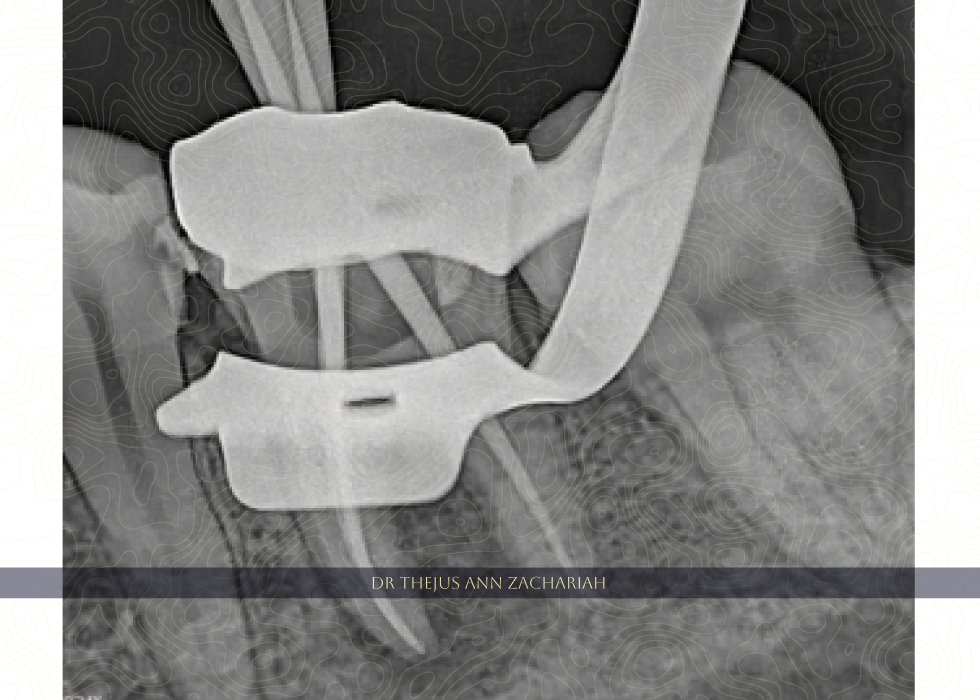

Master Cone